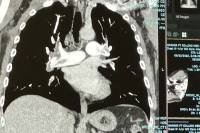

ER Visit for PE

CT Scan Showing PE